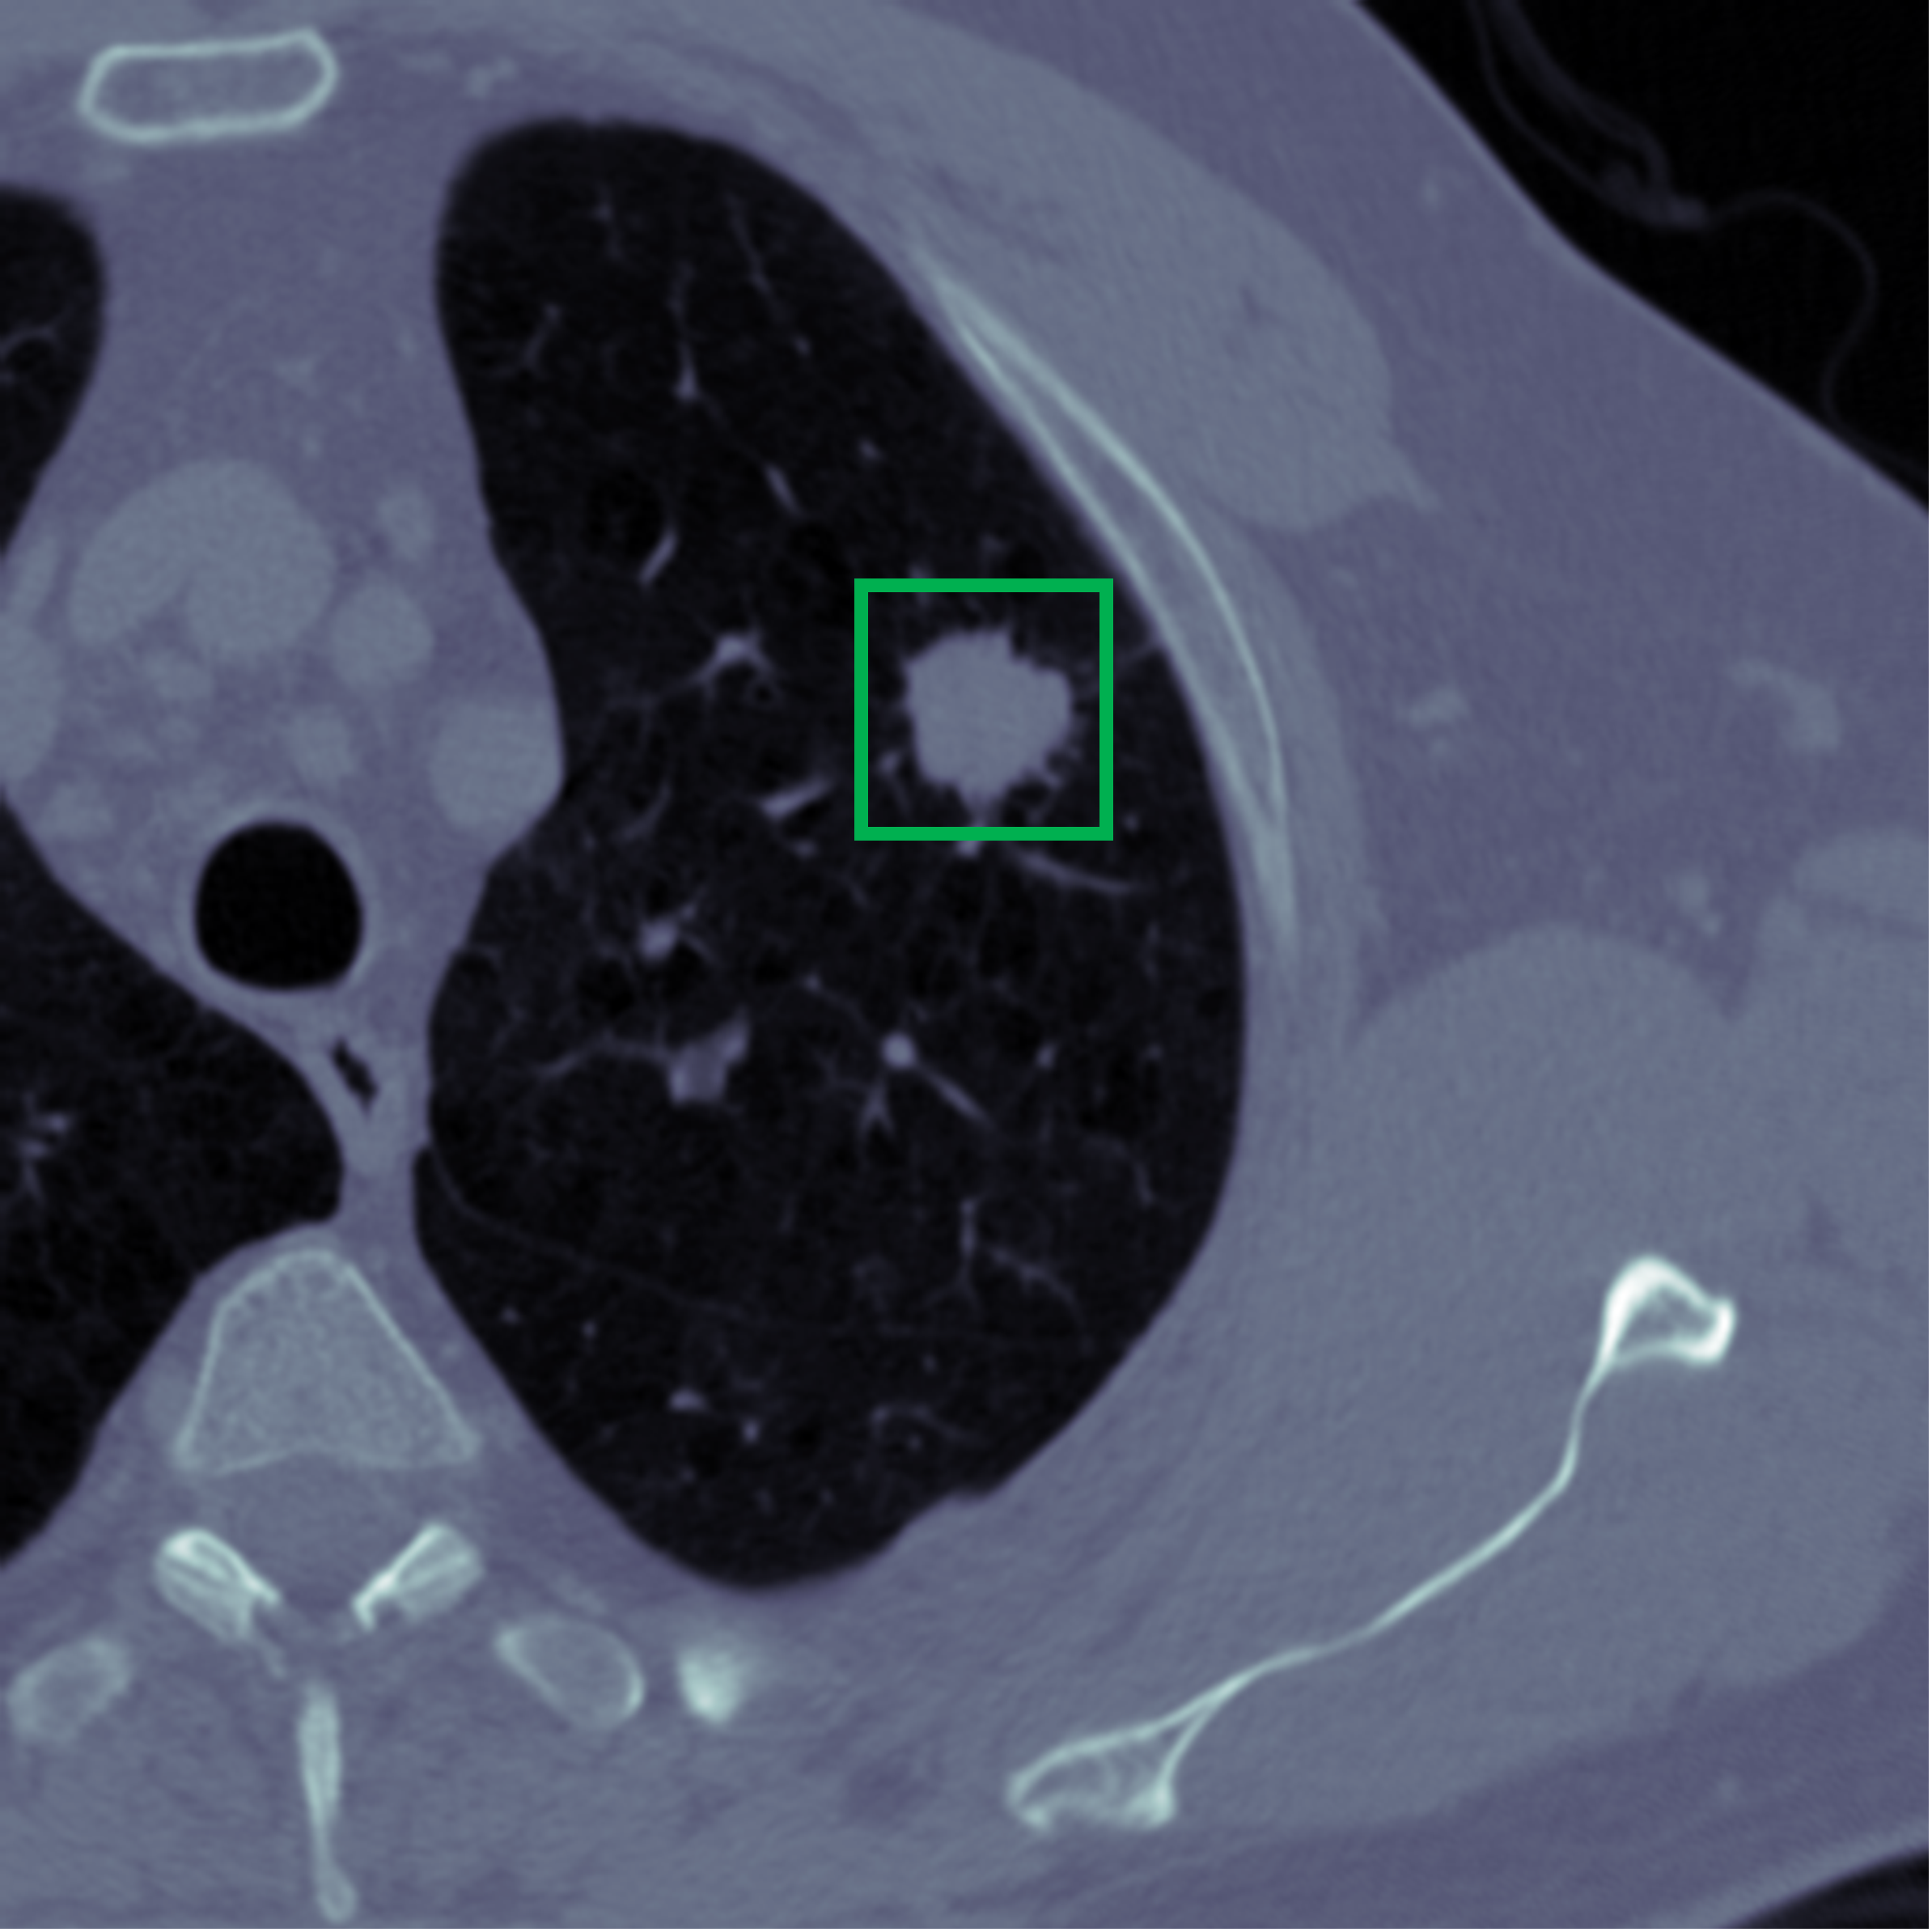

(1) Brain MR (2) Liver MR (3) Liver CT (4) Lung CT

We first introduce a method for connecting the output of a CNN to an ACM, yielding a model for the precise delineation of lesions, to which we refer as Deep Active Lesion Segmentation (DALS) (Figure 4). We then go further to introduce a truly unified framework (Figure 5) that bridges the gap between ACMs and CNNs by leveraging a novel, automatically differentiable level-set ACM with trainable parameters that allows for back-propagation of gradients and can be end-to-end trained along with a backbone CNN from scratch, without any CNN pre-training. The ACM is initialized directly by the CNN and utilizes an energy functional that is locally-tunable by the backbone CNN, through 2D feature maps. Thus, our work overcomes the big hurdle of fully automating the powerful ACM approach to image segmentation. We have applied our proposed framework to the task of building segmentation in aerial images (Figure 6).

Deep Active Lesion Segmentation

[45]: Lesion segmentation is an important problem in computer-assisted diagnosis that remains challenging due to the prevalence of low contrast, irregular boundaries that are unamenable to shape priors. We introduce Deep Active Lesion Segmentation (DALS), a fully automated segmentation framework that leverages the powerful nonlinear feature extraction abilities of FCNs and the precise boundary delineation abilities of ACMs. Our DALS framework benefits from an improved level-set ACM formulation with a per-pixel-parameterized energy functional and a novel multiscale encoder-decoder CNN that learns an initialization probability map along with parameter maps for the ACM. We evaluate our lesion segmentation model on a new Multiorgan Lesion Segmentation (MLS) dataset that contains images of various organs, including brain, liver, and lung, across different imaging modalities—MR and CT. Our results demonstrate favorable performance compared to competing methods, especially for small training datasets. -